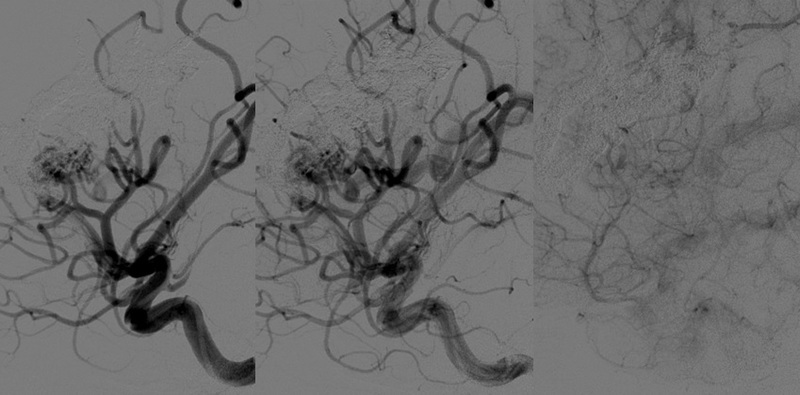

脳梁の大きなAVMが破裂し紹介入院となりました。3~4ヶ月ごとに3回に分けてOnyxを注入しAVMが小さくなった時点でガンマナイフの照射を行い、AVMはほぼ消失しました。現在、後遺症は全くありません。